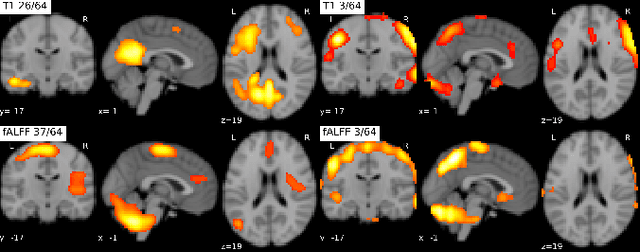

Abstract:Recent neuroimaging studies that focus on predicting brain disorders via modern machine learning approaches commonly include a single modality and rely on supervised over-parameterized models.However, a single modality provides only a limited view of the highly complex brain. Critically, supervised models in clinical settings lack accurate diagnostic labels for training. Coarse labels do not capture the long-tailed spectrum of brain disorder phenotypes, which leads to a loss of generalizability of the model that makes them less useful in diagnostic settings. This work presents a novel multi-scale coordinated framework for learning multiple representations from multimodal neuroimaging data. We propose a general taxonomy of informative inductive biases to capture unique and joint information in multimodal self-supervised fusion. The taxonomy forms a family of decoder-free models with reduced computational complexity and a propensity to capture multi-scale relationships between local and global representations of the multimodal inputs. We conduct a comprehensive evaluation of the taxonomy using functional and structural magnetic resonance imaging (MRI) data across a spectrum of Alzheimer's disease phenotypes and show that self-supervised models reveal disorder-relevant brain regions and multimodal links without access to the labels during pre-training. The proposed multimodal self-supervised learning yields representations with improved classification performance for both modalities. The concomitant rich and flexible unsupervised deep learning framework captures complex multimodal relationships and provides predictive performance that meets or exceeds that of a more narrow supervised classification analysis. We present elaborate quantitative evidence of how this framework can significantly advance our search for missing links in complex brain disorders.

Abstract:Introspection of deep supervised predictive models trained on functional and structural brain imaging may uncover novel markers of Alzheimer's disease (AD). However, supervised training is prone to learning from spurious features (shortcut learning) impairing its value in the discovery process. Deep unsupervised and, recently, contrastive self-supervised approaches, not biased to classification, are better candidates for the task. Their multimodal options specifically offer additional regularization via modality interactions. In this paper, we introduce a way to exhaustively consider multimodal architectures for contrastive self-supervised fusion of fMRI and MRI of AD patients and controls. We show that this multimodal fusion results in representations that improve the results of the downstream classification for both modalities. We investigate the fused self-supervised features projected into the brain space and introduce a numerically stable way to do so.